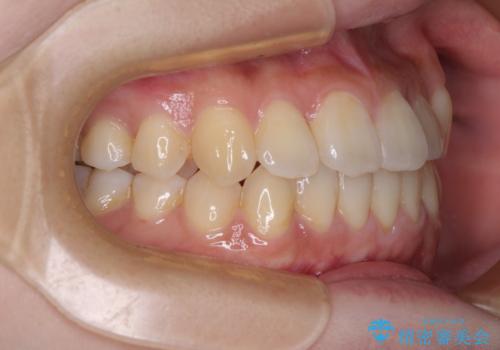

舌側転位している側切歯特有の、切縁の位置が不揃いであったり、根元が内側に引っ込んだ状態であったりという、インビザライン独特の仕上がりになることなく、きれいに整った歯列とすることができました。